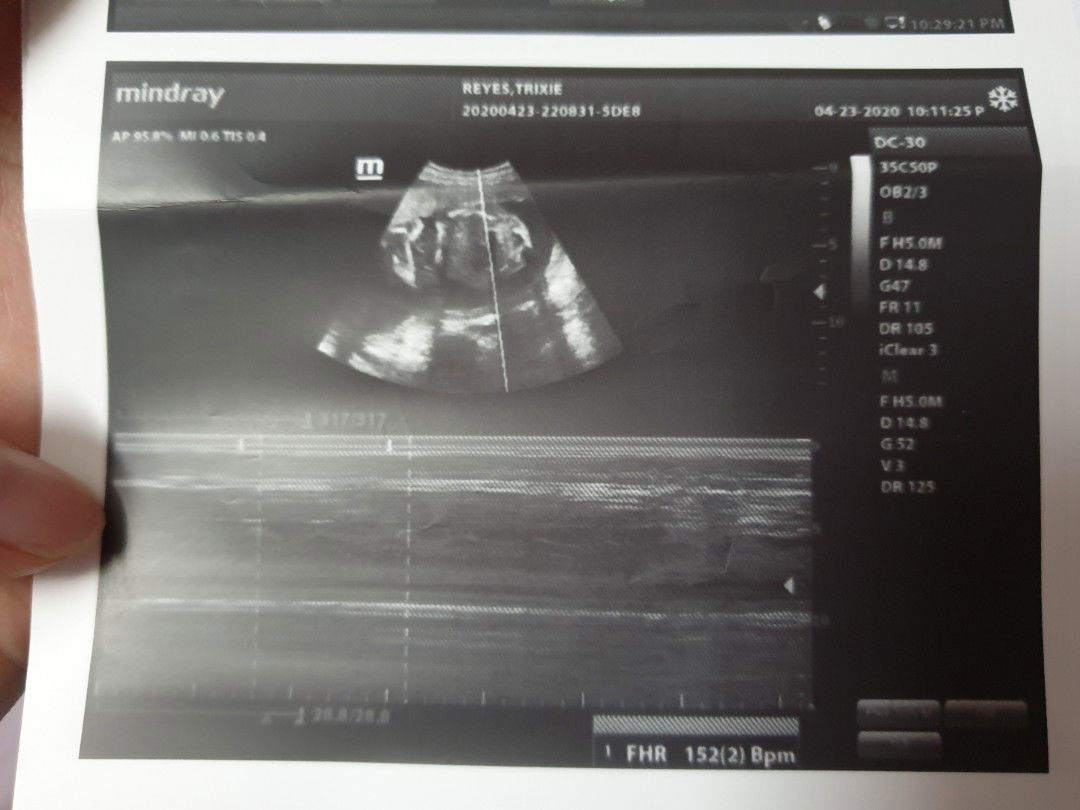

Big possibility na BABY GIRL

Share ko lang ultrasound ni baby today ? hindi makita gender ni baby iniipit nya sa legs nya. Tho sabi ni dra mukang baby girl daw (base sa isang shot na nakuha) No signs of male no pototoy or balls ?kasi malikot si baby nung una tas biglang hindi na gumalaw tulog na pala ?? babalik kami after 2-3 weeks para i sure ang gender pero suspetcha is baby girl ? over all healthy sya kahit ano gender nya no problem na nakita sa ultrasound. ?